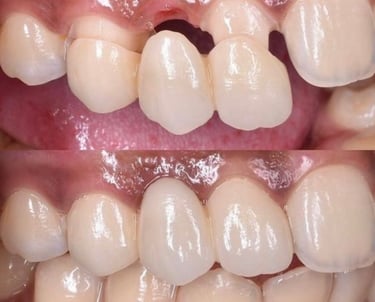

Odontología estética

La odontología estética es la rama de la odontología dedicada a mejorar la apariencia de la sonrisa mediante tratamientos personalizados y avanzados. Incluye procedimientos como blanqueamiento dental, carillas, corrección de forma y tamaño de los dientes, así como el diseño de sonrisa. Nuestro compromiso es brindarte resultados naturales y armoniosos, devolviéndote la confianza y la alegría de lucir una sonrisa perfecta. En nuestra clínica, combinamos tecnología de vanguardia con atención especializada para transformar tu sonrisa y resaltar tu belleza.